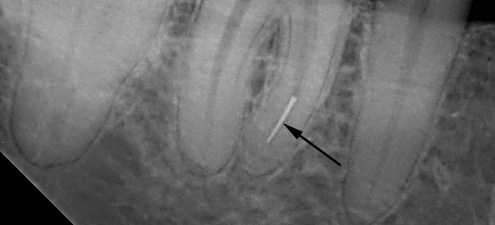

A foto mostra um exemplo de uma ferramenta quebrada em um canal dentário: